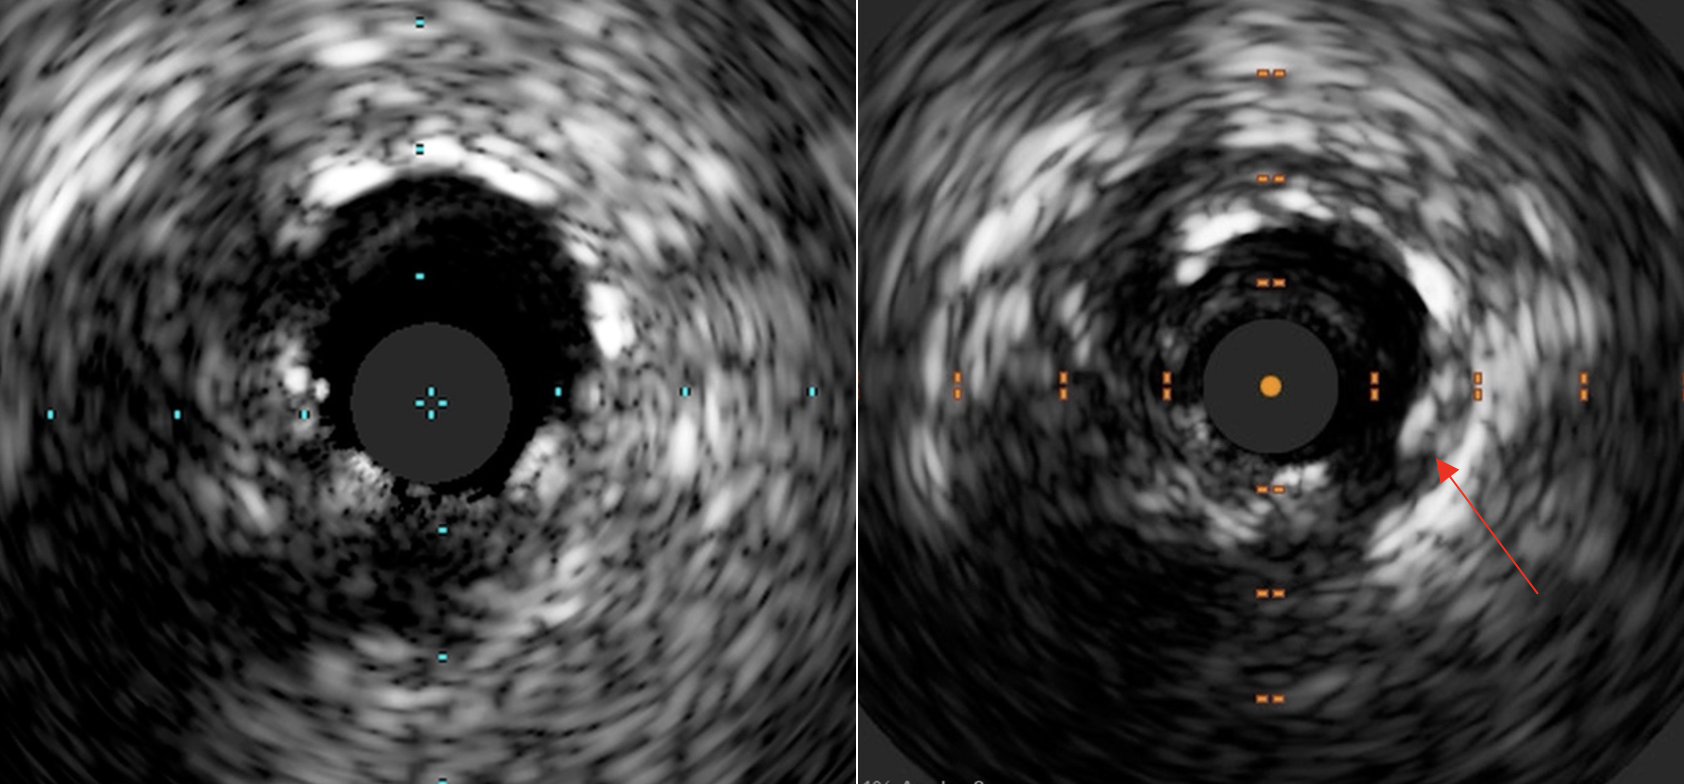

Case Summary

To our best knowledge, this is the first reported case of biopadaptor usage in CTO intervention with a long-term angiographic and intracoronary imaging follow-up. Certain properties of the bioadaptor scaffolds, including the positive adaptive remodelling and restoration of pulsatility of the vessel, was well demonstrated despite in the complex CTO subset of lesion.